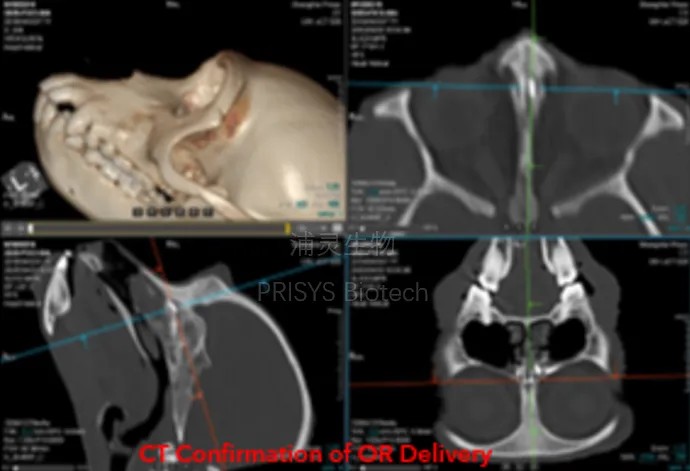

2. 关键技术:经鼻入脑(N2B)递送以跨越血脑屏障